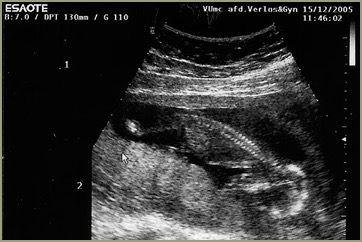

Ik doe de test op zondagochtend, ik zou ongesteld moeten worden maar heb het gevoel dat dat niet gaat gebeuren. Patrick vindt het nog veel te vroeg, maar ik heb er een heel goed gevoel bij. Na al die testen die hieraan vooraf zijn gegaan, na al dat geld dat de firma Clearblue heeft ontvangen van ons, moet dit raak zijn. En dan, dan ben ik zwanger. Gelijk na de eerste keer, een kans van 1 op 5. Alsof deze kindjes perse een Françaises willen zijn. Ja meisjes, zo voelt het meteen. Bij de echo een aantal weken later horen we definitief hoeveel het er zijn. Omdat mijn lichaam door de vele tweelingen in de familie van zowel vaders als moederskant vier eitjes had aangemaakt, zijn we heel benieuwd naar het uiteindelijke aantal. Zonder toegevoegde hormonen toch zoveel eitjes, ook de artsen in het ziekenhuis zijn benieuwd. Twee eitjes zijn aangeslagen, met andere woorden, twee kindjes gaan er groeien in mijn buik.

Na 10 weken begin ik ’s avonds heel erg te bloeden, geen kramp, alleen maar heel veel bloed. We zijn in alle staten en bellen meteen het ziekenhuis. We worden verwacht op de eerste hulp, dus in de auto en scheuren maar. Daar aangekomen moeten we idioot lang wachten, maar als er dan eindelijk na 2,5 uur een echo wordt gemaakt zijn er nog steeds twee hele duidelijke hartjes te zien, alles is goed, er wordt alleen een grote bloedprop weggehaald en we kunnen weer naar huis.

Echo-Mina